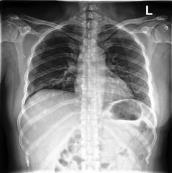

Large numbers of labeled medical images are essential for the accurate detection of anomalies, but manual annotation is labor-intensive and time-consuming. Self-supervised learning (SSL) is a training method to learn data-specific features without manual annotation. Several SSL-based models have been employed in medical image anomaly detection. These SSL methods effectively learn representations in several field-specific images, such as natural and industrial product images. However, owing to the requirement of medical expertise, typical SSL-based models are inefficient in medical image anomaly detection. We present an SSL-based model that enables anatomical structure-based unsupervised anomaly detection (UAD). The model employs the anatomy-aware pasting (AnatPaste) augmentation tool. AnatPaste employs a threshold-based lung segmentation pretext task to create anomalies in normal chest radiographs, which are used for model pretraining. These anomalies are similar to real anomalies and help the model recognize them. We evaluate our model on three opensource chest radiograph datasets. Our model exhibit area under curves (AUC) of 92.1%, 78.7%, and 81.9%, which are the highest among existing UAD models. This is the first SSL model to employ anatomical information as a pretext task. AnatPaste can be applied in various deep learning models and downstream tasks. It can be employed for other modalities by fixing appropriate segmentation. Our code is publicly available at: https://github.com/jun-sato/AnatPaste.